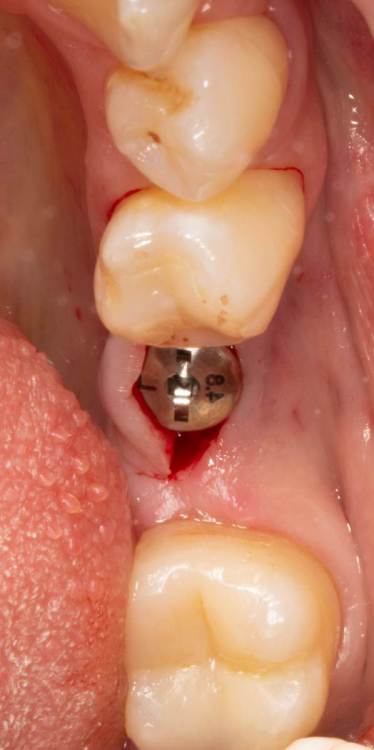

Женька Опубликовано 19 июня, 2023 Поделиться Опубликовано 19 июня, 2023 Здравствуйте, коллеги. Примерно с нового года начал ставить ТЛ имплантаты Дентиум. Что-то под заглушку (не поймал торки, представляете?). Что-то на низких формирвателях. И вот пришла пора протезирования, но отпустить к ортопеду не подготовив десну - не получается. Создал сам себе проблем, сегодня вот исправлял. Получилось неплохо? 3 Ссылка на комментарий

Женька Опубликовано 20 июня, 2023 Автор Поделиться Опубликовано 20 июня, 2023 @АнтонТЛТ мы же позиционируем платформу относительно зенита? Есть ли разница тогда, какой имплантат мы выбираем? Вообще весь смысл здесь был заложен в том, что толщина гребня была не очень. Хотелось поставить тонкий имплантат 3.6. Но рисковать тонкой платформой не хотелось, поэтому выбор пал на 4.8 платформу ТЛ и тело имплантата 3.6 1 Ссылка на комментарий